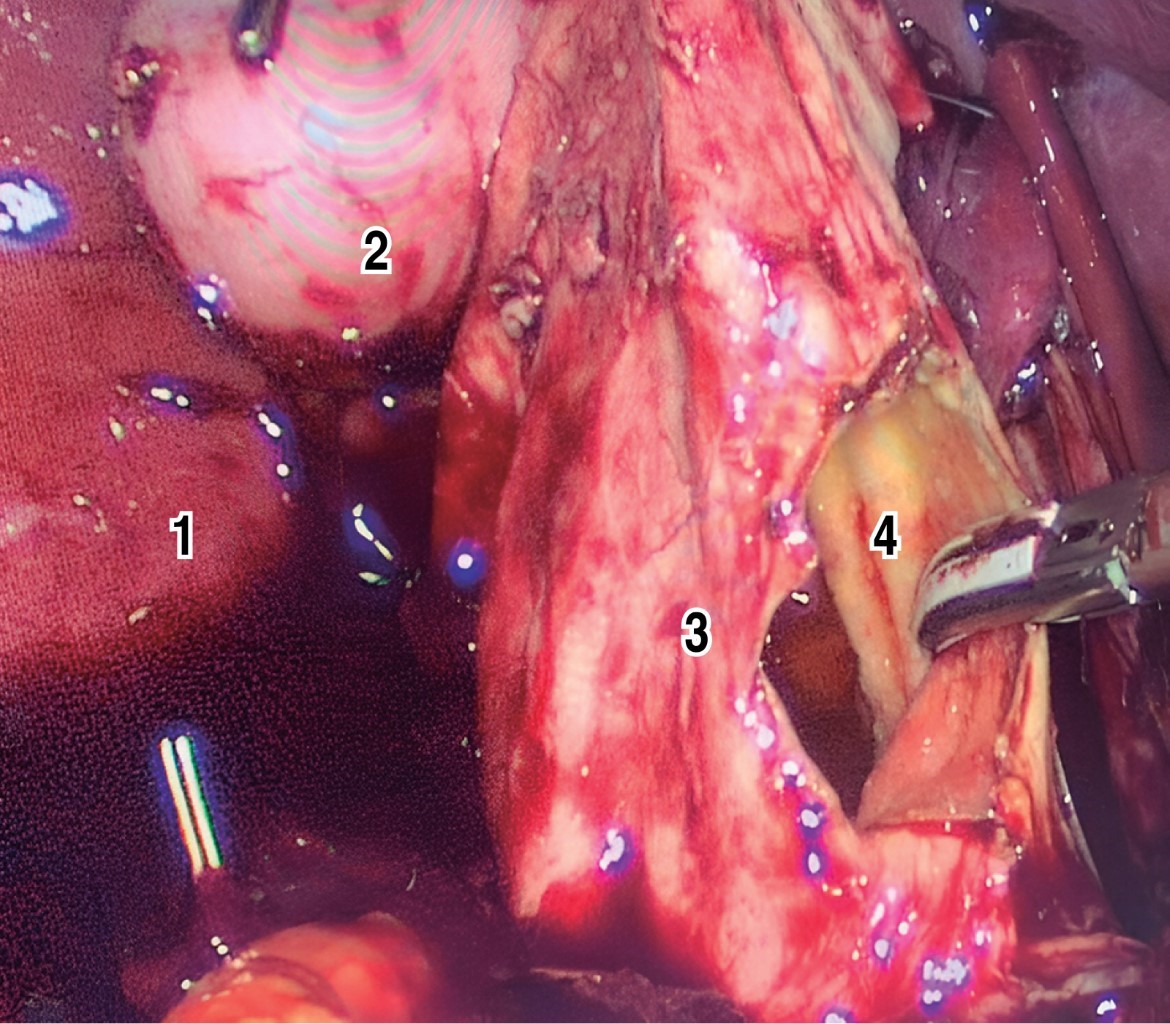

Se programó una resección electiva por vía laparoscópica (Figura 5) tras completar un protocolo preoperatorio exhaustivo. Los hallazgos intraoperatorios evidenciaron el QC-IVA-Todani-modificada, con una vesícula biliar atrófica. Se inició la disección de la cápsula del quiste intentando separarla de las estructuras vasculares (vena porta y arteria hepática). Se decidió abrir el quiste para facilitar su disección, pero debido a su fuerte adherencia y vascularización, con un sangrado escaso pero continuo, se convirtió en una cirugía abierta mediante una incisión tipo Kocher.

Se continuó la disección del quiste separándolo de la vena porta sin dañarla. A través de la apertura del quiste, se introdujo un dilatador de Bakes para identificar y canalizar los conductos hepáticos derecho e izquierdo dilatados. Luego se realizó la extirpación del quiste de colédoco desde la bifurcación de ambos conductos intrahepáticos hasta el borde duodenal, donde se practicó una sutura continua con polidioxanona incluyendo el último centímetro del conducto colédoco, realizando así una extirpación completa del quiste, incluyendo la vesícula biliar. Para finalizar, se realizó una derivación biliodigestiva en Y de Roux, con un asa yeyunal a 50 cm del Treitz, y un asa para el drenaje biliar de 50 cm, utilizando una engrapadora lineal de 60 mm en la hepático-yeyuno anastomosis.